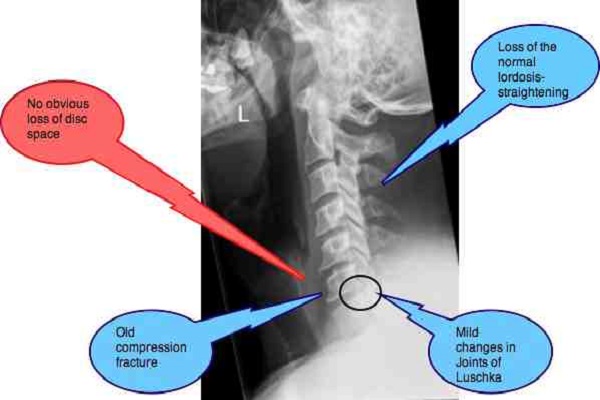

Đốt sống cổ có 7 đốt. C4-5 có đĩa đệm thì gây đau, vậy C1-2 không có đĩa đệm thì có gây đau không?

Bác sĩ hồi đáp